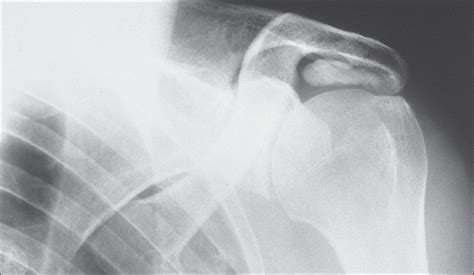

To confirm the diagnosis of calcium deposits in shoulder, an orthopedic specialist will usually conduct a physical examination followed by imaging tests. Because these deposits are essentially mineral structures, they show up very clearly on standard medical imaging.

X-ray The most common tool; clearly shows the shape and size of the calcium deposit.